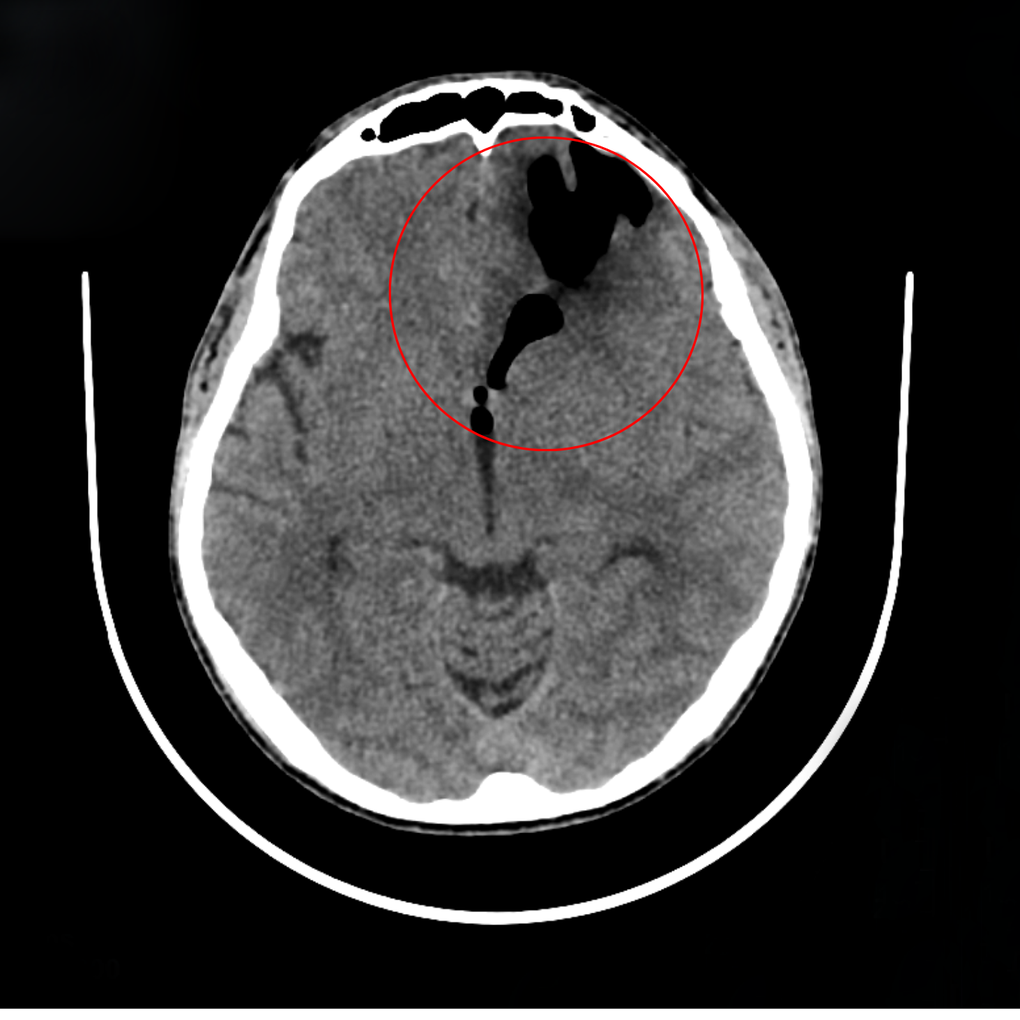

Theo PGS. Hà Kim Trung - Phó giám đốc BVĐK Hồng Ngọc - Phúc Trường Minh, chuyên gia hơn 30 năm kinh nghiệm phẫu thuật thần kinh sọ não, quá trình thăm khám thần kinh không phát hiện triệu chứng bất thường. Kết quả phim chụp CT não cho thấy khối tụ khí lớn trong sọ ở vùng trán trái, chèn ép mạnh lên thùy trán và não thất. Sau 5 ngày theo dõi, triệu chứng đau đầu và chảy dịch mũi không thuyên giảm, cho thấy dấu hiệu của rò dịch não tủy muộn sau chấn thương sọ não.

Tụ khí do rò dịch não gây chảy dịch, đau đầu, mệt mỏi (Ảnh: BVCC).